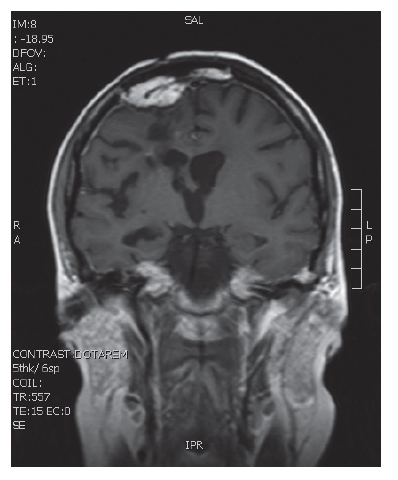

V naší kazuistice prezentujeme 25letou pacientku s negativní onkologickou rodinnou anamnézou, která dosud vážněji nestonala. Udávala asi 3 měsíce progredující bolesti hlavy a krční páteře, zvracení, postupně rozmazané vidění a parestezie horních končetin. Byla provedena magnetická rezonance, na které diagnostikován tumor mozku ve frontálním laloku vpravo, vyplňující frontální roh postranní komory velikosti 6x5 cm, midline shift, mass efekt. Dne 23. 9. 2013 ji byla na neurochirurgické klinice provedena neradikální exstirpace tumoru z parasagitální kraniotomie. Histologicky byl prokázán glioblastom multiforme gr. IV. Od 30. 10. 2013 do 12. 12. 2013 absolvovala konkomitantní radiochemoterapii (radioterapie do CLD 60,0 Gy) s temozolomidem (75 mg/m2 per os D1-42). Od ledna do dubna 2014 pokračovala v chemoterapii temozolomid solo v dávce 150 mg/m2, resp. od 2. cyklu 200 mg/m2 D1-5 ( Temodal tbl, celkem 4x). Na kontrolní MRI mozku ze dne 20. 5. 2014 byla prokázána progrese rezidua. Dne 4. 6. 2014 podstoupila druhou operaci, histologicky verifikován glioblastom multiforme s přechodem v gliosarkom. Snažili jsme se získat informace ze zahraniční literatury s léčbou gliosarkomu, bohužel se jedná o velmi vzácné onemocnění a údajů není mnoho. Nakonec byla zvolena léčba podle protokolu ICE (ifosfamid, carboplatina, etoposid), který je obdobou režimu PEI. Dávky: ifosfamid 1000 mg/m2 D1-3, carboplatina 110 mg/m2 D1 a etoposid 100 mg/m2 D1-3 v pětitýdenním cyklu. Pacientka zahájila 1. sérii od 1.7.2014 s podporou G-CSF (Neulasta s.c.). Léčbu tolerovala dobře, bez akutních či pozdních vedlejších nežádoucích účinků a významné hematologické toxicity. Po 3 cyklech podstoupila kontrolní MRI, kde popsána parciální regrese periferního sycení – rezidua tumoru. Po dalších 3 cyklech chemoterapie provedena restagingová MRI, kde popsána opět mírná regrese rezidua tumoru. Celkový stav pacientky se během léčby postupně zlepšoval, je mobilní, bez psychoorganického syndromu. Byly vysazeny kortikoidy, což vedlo k ústupu cushingoidního syndromu. Bylo rozhodnuto o pokračování v dalších 2 cyklech udržovací chemoterapie, na kontrolní MRI ze 14. 4. 2015 a 7. 7. 2015 popsána stabilizace onemocnění.